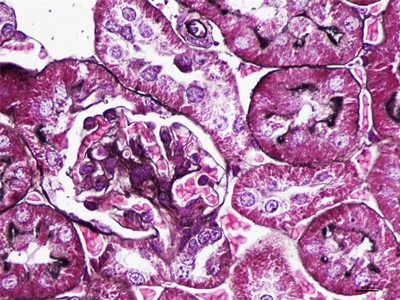

HE染色简称苏木精是是一种由碱性染液苏木精和酸性染液伊红构成的一种染色方法。是通显微镜下观察病理切片里病变的组织学形态变化来诊断疾病的,适用于胚胎学、病理学,生物医学,病理学教学与科研。HE染色对碱性染料和酸性染料亲和力都比较弱的现象称为中性。组织切片苏木素染色、分化与反蓝:将水化后的组织样本的切片使用PBS溶液浸泡清洗,每次浸泡5min,总共清洗3次。之后用移液枪吸取已经预先配置好的苏木素染色液,每个组织切片滴加100ul,充分染色10min。切片经HE染色后,要彻底脱水透明,才能用云南中性树胶封盖。he染色对于贴壁生长细胞,胰酶消化,调整细胞浓度约1×105/ml,滴加于盖玻片上(置于6孔板中),培养相应时间后,取出细胞爬片,用PBS 洗涤3次。着色情况与组织或细胞的种类有关。切片在苏木素染液中停留过长;或切片太厚;或分化时间太短。这种情况首先镜下看看切片厚度(最佳厚度1-2层细胞核),要么重新染色,要么重新制片。染色的最终结果是:细胞核呈蓝色、胞质、肌纤维、胶原纤维和红细胞呈深浅不一样的红色,病理技术服务提醒:在进行HE染色需要染色时间,脱水,染色时间不一样,需要等 ,明确HE评判标准。